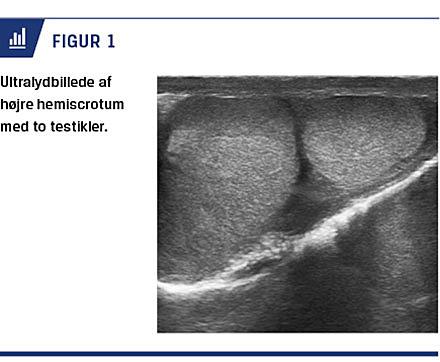

En 14-årig dreng blev af egen læge henvist til et organkirurgisk børneambulatorium pga. palpatorisk fund af en tredje testikel i scrotum. Han blev som treårig ad to omgange opereret for højresidigt ingvinalhernie. Der blev på dette tidspunkt ikke beskrevet polyorkisme i journalen. Patienten blev indkaldt til en ambulant undersøgelse, hvor der blev fundet en normalt udseende penis og ved palpering en normal testikel i venstre skrotalhalvdel. I højre skrotalhalvdel palperedes to udfyldninger henover hinanden, begge glatte og i konsistens som normale testikler. Den nederste var mindre end den øverste. Der blev ikke fundet nogen tegn til recidiv af herniet. Herefter blev han henvist til en ultralydskanning af scrotum (Figur 1).

Ved ultralydskanningen påviste man to testikler med normal struktur og en fælles bitestikel i højre side af scrotum. Efterfølgende blev patienten viderehenvist til et urologisk ambulatorium, hvor man genfandt to

testikler på højre side og en fælles ductus deferens. Testiklerne målte ca. 3 × 2 cm og 2 × 2 cm.